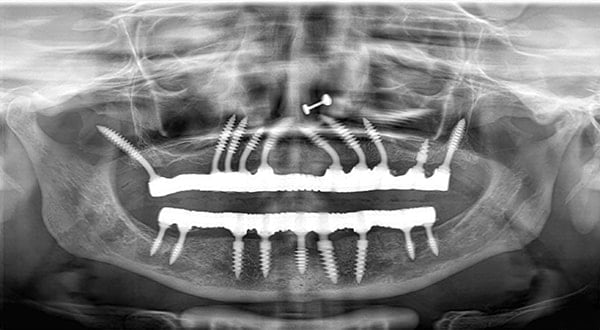

Progressive single spiral threads. Higher Bone Implant contact. Improved primary stability. More Resistance to Tensile & Compressive forces. Flame shape threading pattern enables higher primary stability.

Optimum basal bone engagement